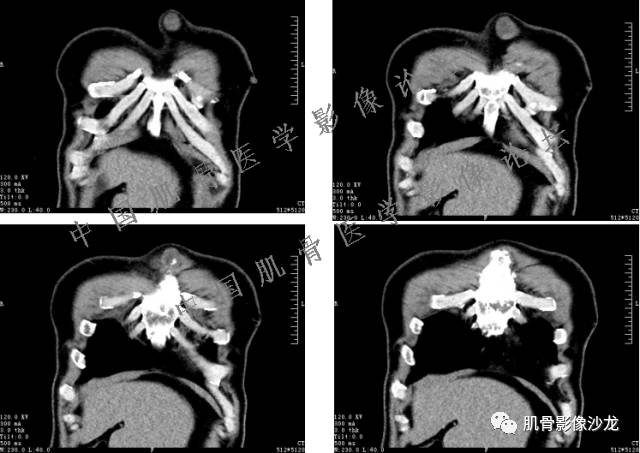

患者于2月前无明显诱因下出现腰骶部疼痛,夜间为重,逐渐加重伴左下肢麻木、疼痛,并有行走活动受限,在我院就诊,摄腰椎及骶髂部CT提示:腰椎骨质退变,腰3-4、4-5椎间盘膨出,骶髂关节炎。自用非甾体抗炎药无好转,再次来院就诊,门诊拟“骶髂关节炎”收住我科。病程无间歇性跛行,大小便正常。

专科检查:神清,脊柱无侧弯后凸畸形,椎体各节段无压、叩痛,双侧棘突旁无压痛,双侧骶髂关节压痛明显,左下肢放射痛,浅感觉较健侧减退,腰椎前屈后伸活动受限,膝、跟腱反射正常。

辅助检查:腰椎及骶髂部CT提示:腰椎骨质退变,腰3-4、4-5椎间盘膨出,骶髂关节炎。

雪舞 :第二例,位于骶骨,有骨质破坏并有软组织肿块,软组织肿块边界清

向以四 : 病例2 感染性骶髂关节炎 TB可能大,左侧梨状肌受累、肿胀增粗,并见低密度脓肿?

西门吹雪:考虑恶性肿瘤 的确有些难

晴朗 :倾向肉瘤

医影在线 : 转移瘤要除外

致远 : 或者软骨肉瘤

张小林:炎性病变和肿瘤的鉴别

飞鹰行动 :有一定的骨质硬化,骨肉瘤及软骨肉瘤可能性大 晴朗: 有骨膜反应,有软组织肿块

雪舞: 第二例我们能够看到破坏与软组织肿块不成比例,软组织肿块大,破坏小

医影在线: 病变无明显钙化

雪舞 :第二例挺难的,骨质破坏是溶骨性的,局部皮质中断,软组织肿块外缘光滑

医影在线 :无软骨钙化

飞鹰行动 :有的软骨肉瘤可以没有钙化

晴朗 :软骨基质不一定都是钙化的